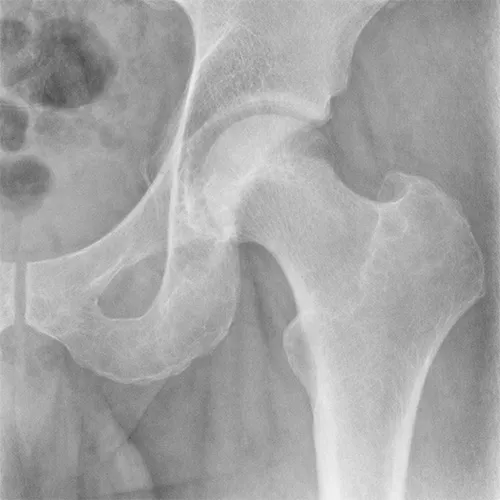

Intervenții chirurgicale de artroplastii de șold/genunchi, osteosinteze complexe, artroscopii. Raportare cazuri, plan terapeutic, documente de externare. Consultații în ambulatoriu, diagnostic și stabilirea conduitei terapeutice.

Dual Mobility Cups in High-Risk Revision Hip Arthroplasty: A Case Series Highlighting Stability and Biomechanical Restoration